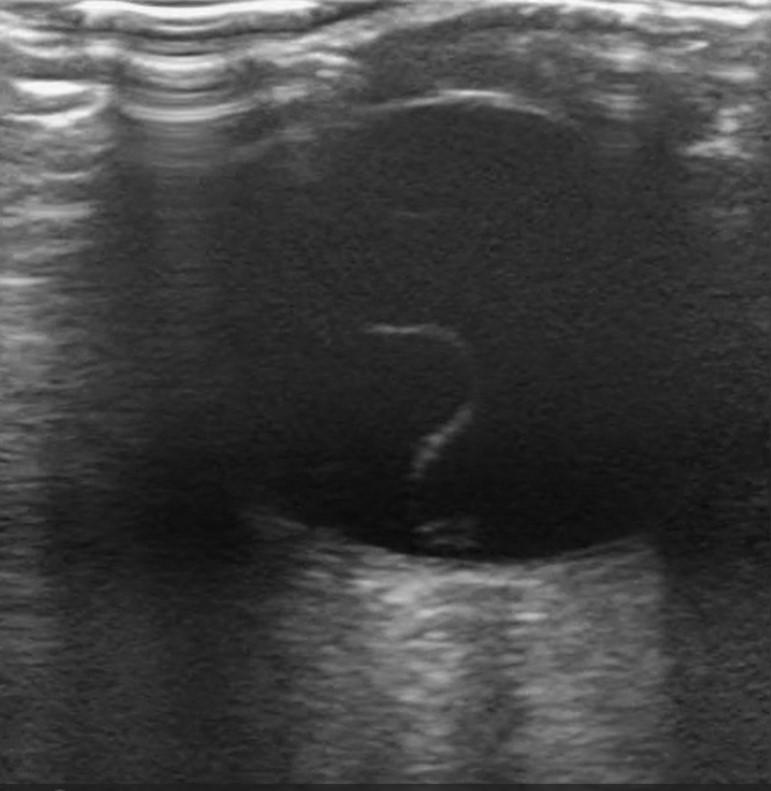

Not Just Small Adults: Tailoring Point-of-Care Ultrasound Skills for Pediatric Patients

Point-of-Care Ultrasound in Acute Monocular Vision Loss